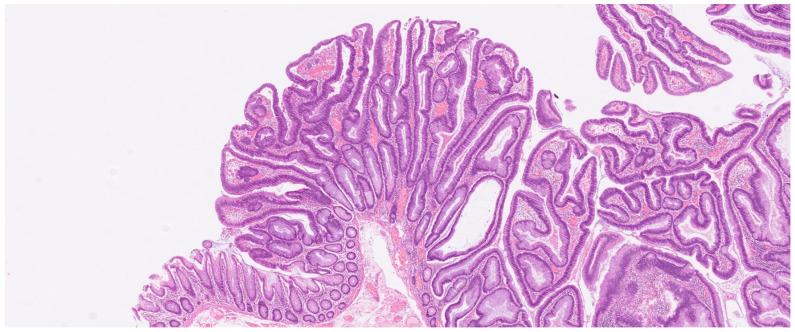

To assess the use of quantitative diffusion-weighted MRI (DW-MRI) as a diagnostic imaging biomarker in differentiating between benign colon adenoma, early, and advanced cancer of the colon, as well as predicting lymph node involvement, and finally comparing mucinous-producing colon cancer with adenomas and non-mucinous colon cancer.

METHOD

Patients with a confirmed tumor on colonoscopy were eligible for inclusion in this study. Using a 3.0 Tesla MRI machine, the main tumor mean apparent diffusion coefficient (mADC) was obtained. Surgically resected tumor specimens served as an endpoint, except in mucinous colon cancers, which were classified based on T2 images.

RESULTS

A total of 152 patients were included in the study population. The mean age was 71 years. A statistically significant mADC mean difference of -282 × 10 mm/s [-419--144 95% CI, < 0.001] was found between colon adenomas and early colon cancer, with an AUC of 0.80 [0.68-0.93 95% CI] and an optimal cut off value of 1018 × 10 mm/s. Only a small statistically significant difference ( = 0.039) in mADC was found between benign tumors and mucinous colon cancer. We found no statistical difference in mADC mean values between early and advanced colon cancer, and between colon cancer with and without lymph node involvement.

CONCLUSION

Quantitative DW-MRI is potentially useful for determining whether a colonic tumor is benign or malignant. Mucinous colon cancer shows less diffusion restriction when compared to non-mucinous colon cancer, a potential pitfall.